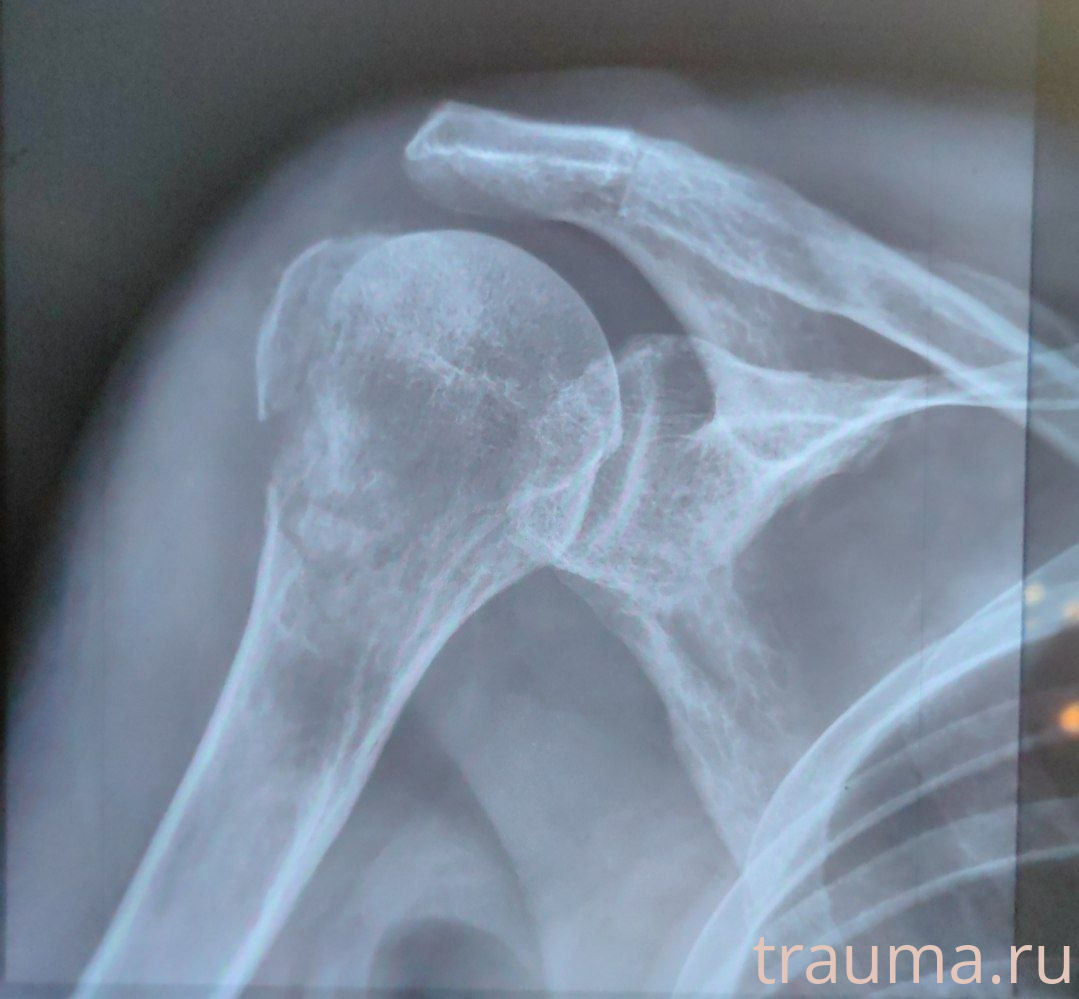

Рентгенограммы

Рентген на дому: по вашему адресу приезжает врач-рентгенолог, травматолог-ортопед с мобильным рентгеновским аппаратом, проводит диагностику травмы или заболевания, делает необходимые рентгенограммы, дает рекомендации по дальнейшему лечению. Получить качественные снимки в домашних условиях возможно благодаря уникальной методике, разработанной МосРентген Центром для института  Склифосовского

Яркость: 1   Контраст: 1   Инвертировать: 0 Увеличение: 1

Перетаскивайте мышь вверх/вниз для контраста, влево/право для яркости. Прокрутка колесом изменяет масштаб. Нажмите Сбросить для возврата к исходному изображению. При увеличении держите мышь в той области, которую хотите рассмотреть.